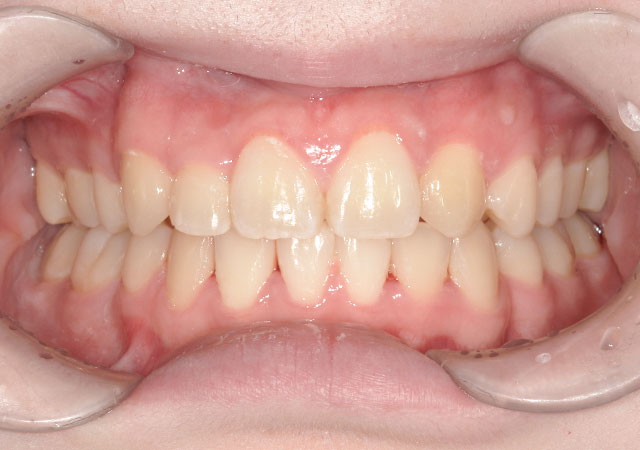

【治療内容】八重歯(叢生)の患者さんです。マウスピース部分矯正(インビザラインGO)で歯並びを治しました。

【費用】マウスピース部分矯正(インビザラインGO) 390,000円(税抜)

【リスク】マウスピースを1日22時間入れなければいけないため、装着時間を厳守しないと矯正治療が進みません。